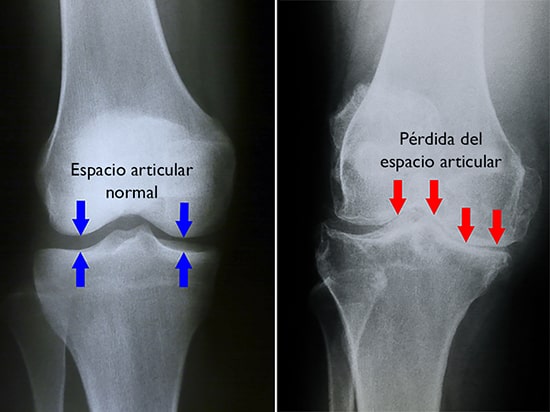

Radiografías. Estos estudios brindan imágenes de estructuras densas, como los huesos. Aunque los quistes no se pueden ver en una radiografía, su médico podría indicarle una para detectar si hay un estrechamiento del espacio articular y otros signos deartritis en la articulación.

normal and arthritic knee

(Izquierda) En esta radiografía de una rodilla sana, el espacio entre los huesos indica que el cartílago está sano. (Derecha) Esta radiografía de una rodilla con artritis muestra que hay una pérdida importante del espacio articular.